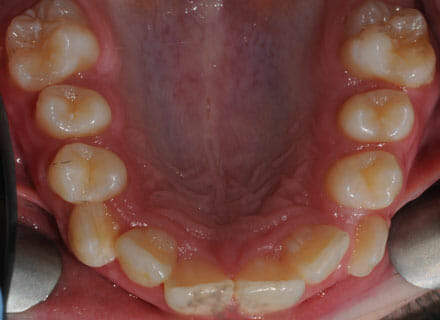

This lady hated her very uneven smile, all the teeth sticking out at the sides, teeth bunched together and uneven. We fitted clear brackets and a wire on the inside in the upper jaw in the roof of the mouth and in under 18 months the teeth were perfectly aligned and the patient’s smile was changed forever.